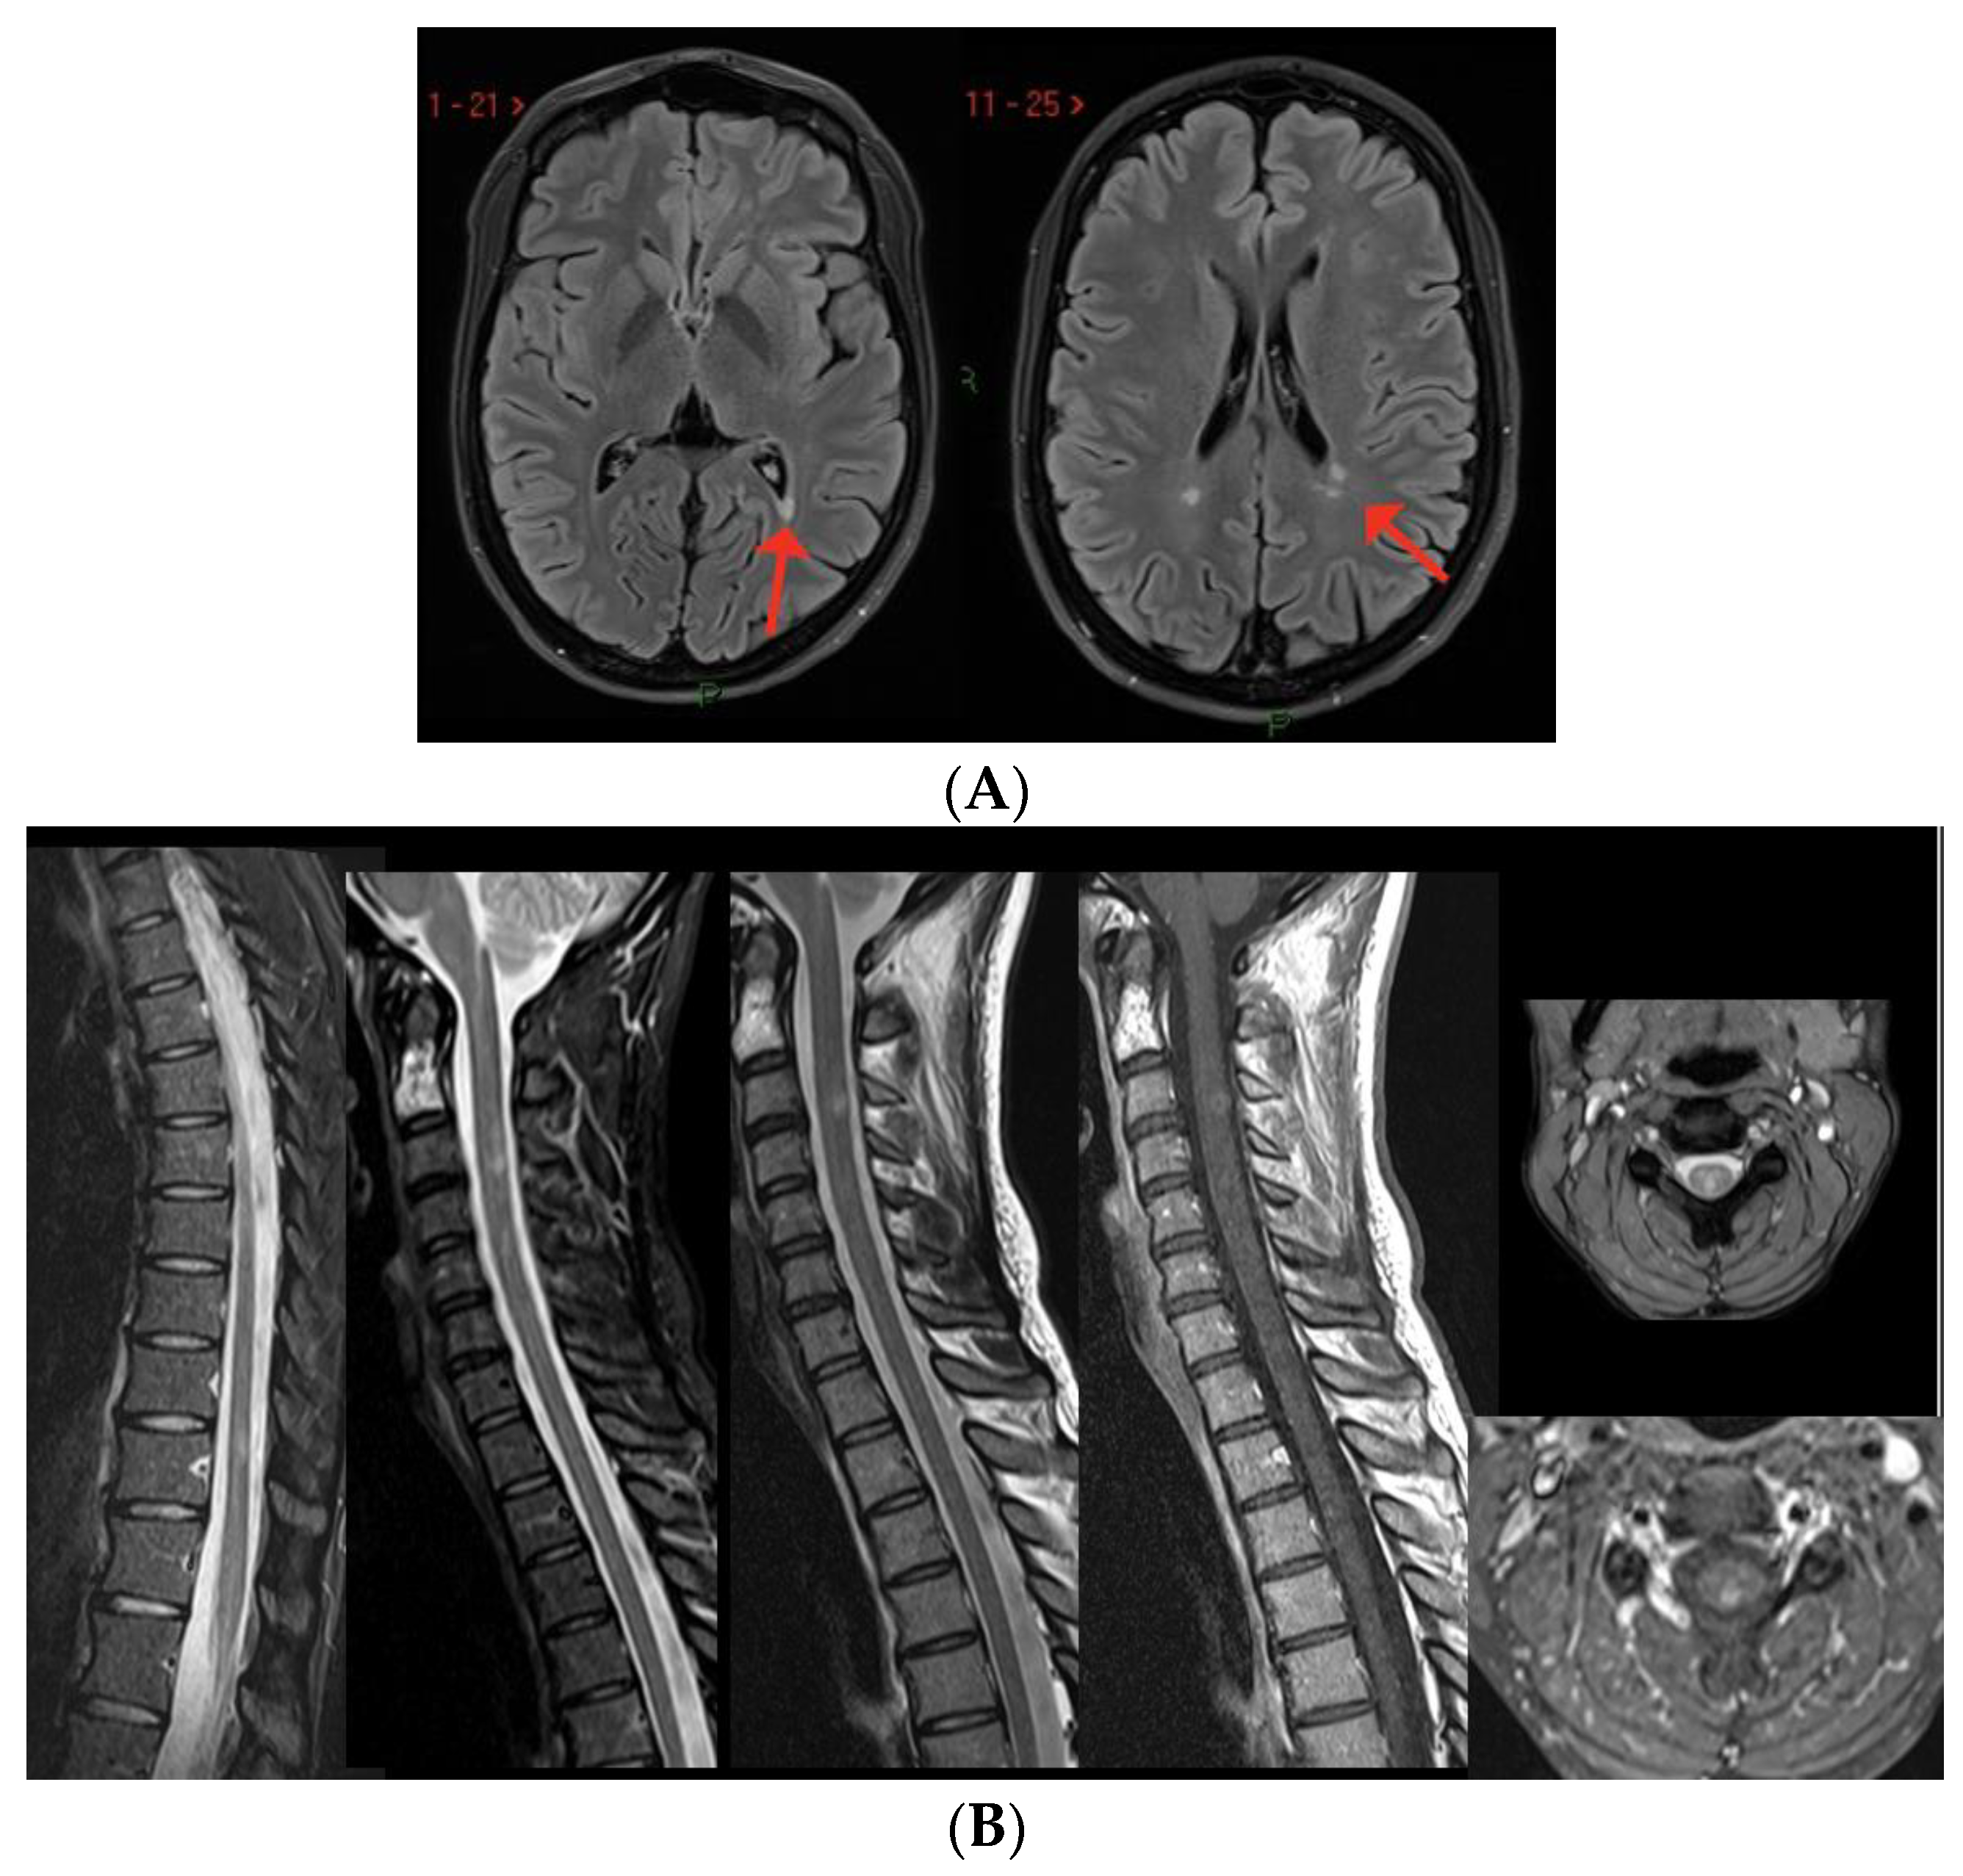

2. MS Onset after SARS-CoV-2 Exposure

| Case 1 | 2 weeks | BS (dyplopia) | - | + | + | - | +/+ |

| Moore et al. [52] | 2 weeks | BS (dyplopia) | BS, ST | + | + | NA | +/+ |

| Yavari et al. [53] | 3 weeks | BS (dyplopia) | ST | + | NA | NA | -/- |

| Carta et al. [54] | concomitant | BS (dyplopia) | ST ^ | + | NA | -/- | |

| Pignolo et al. [55] 1st case | 8 weeks | BS (facial palsy) | - | + | + | - | +/+ |

| Ismail et al. [76]. | 8 weeks | Cerebellum | - | + | + | - | -/- |

| Case 2 | 2 weeks | ON | - SC | + | - | - | +/+ |

| $ Case 3 | 2 weeks | ON | - | + | + | - | +/+ |

| Palao et al. [56] | 2 weeks | ON | ST | + | + | - | +/+ |

| Sarwar et al. [57] | 3 weeks | ON and unilateral motor deficit | ST | + | NA | NA | -/- |

| Case 4 | 4 weeks | SC | SC | + | + | + | +/+ |

| Fragoso et al. [58] | 6 months | SC | ST, SC | + | + | - | +/+ |

| Avila et al. [59] * | 2–6 weeks | 40% SC 40% ON 20% BS | NA | NA | + | 80% - 20% + | NA/+ |

| Feizi et al. [60] | 1 week | SC | SC | + | + | NA | +/+ |